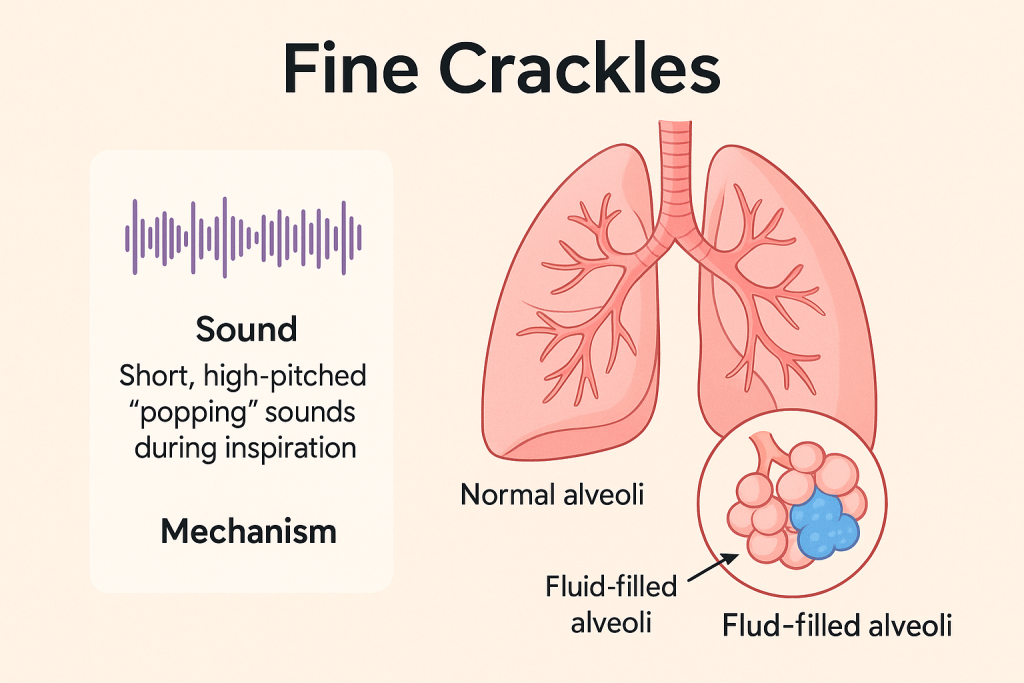

Fine crackles (ફાઇન ક્રેકલ્સ):

- ફાઇન ક્રેકલ્સ (Fine Crackles) એ એક પ્રકારનો અબનોર્મલ ડિસ્કન્ટિન્યુઅસ (Discontinuous) બ્રેથ સાઉન્ડ છે, જે Short, Soft, High-pitched Popping or Crackling જેવા અવાજ રૂપે સાંભળાય છે.

- આ અવાજ સામાન્ય રીતે Inspiration (શ્વાસ લેતી વખતે) દરમ્યાન સાંભળાય છે, ખાસ કરીને Lungsના બેઝ (Bases) પર.

તે દર્શાવે છે કે lungsના નાના એરવે અથવા એલ્વિઓલાઈ (Alveoli) માં પ્રવાહી (Fluid) અથવા કોલેપ્સ થયેલા એર સ્પેસ (Collapsed Air Spaces) ખુલતાં હોય છે.